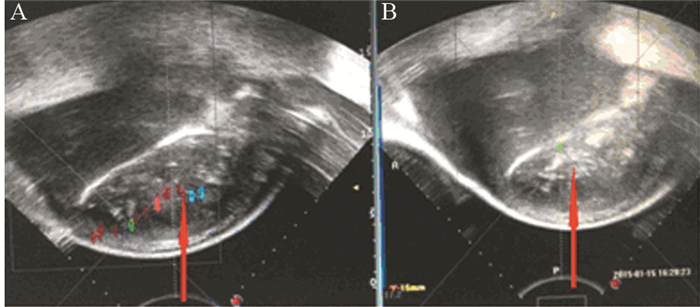

治疗后患者左肩可自由活动,疼痛明显减轻,疼痛VAS评分0~2分,舒乐安定再次减半,每晚0.5 mg口服,奥施康定减量,每12 h 10 mg镇痛治疗。治疗前后的影像学变化见图 1、2。

| 图 1 第1次HIFU治疗前 (A) 后 (B) 的术中影像学变化 Figure 1 Intraoperative imaging changes before (A) and after (B) the first HIFU treatment |